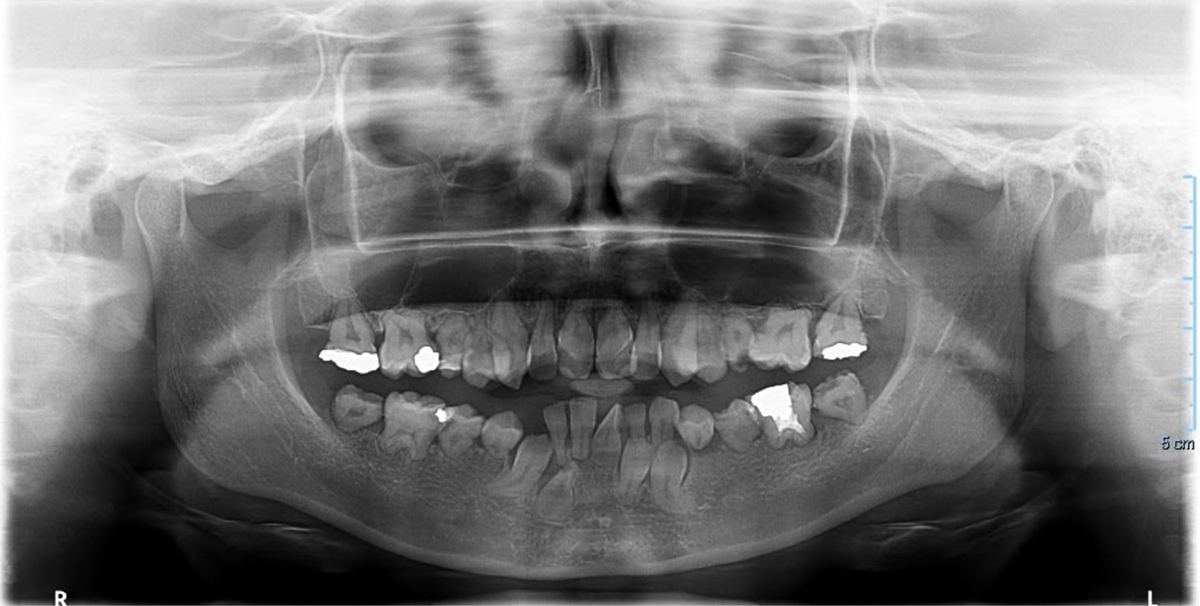

Panoramic radiograph (October 2018) of Case 1 prior to dental extractions, showing generalized root and crown dysplasia.